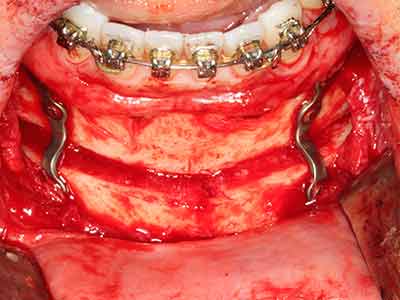

Quando le procedure chirurgiche vengono eseguite sull'osso nelle immediate vicinanze di strutture sensibili, come vasi sanguigni o nervi, gli strumenti rotanti pongono un rischio significativo di lesione iatrogena. I dispositivi piezoelettrici possono essere utili per la preparazione delle coperture ossee e la rimozione del tessuto duro in prossimità dei nervi, in particolare per la loro esposizione dopo una lesione iatrogena, ma anche durante la lateralizzazione dei nervi per le procedure di resezione e ricostruzione o il posizionamento di impianti (figg. 17-20). Il contatto leggero tra puntina piezoelettrica e nervo non causa generalmente danni, ma se si procede senza prestare attenzione con movimenti a sega o raccordi con residui di substrati ossei possono verificarsi danni al nervo temporanei o anche permanenti. Il rischio di danno, tuttavia, è considerato sostanzialmente inferiore al rischio presente utilizzando seghe o frese (Pereira, Gealh et al. 2014).